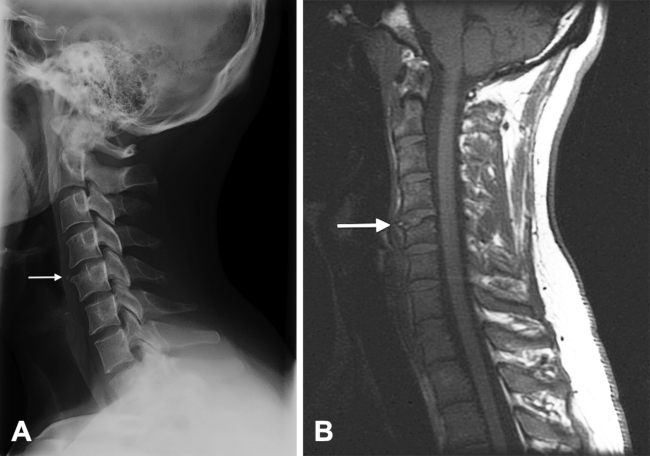

En la radiografía simple lateral de columna cervical se observa, como hallazgo casual, un defecto óseo de forma triangular en el borde anterosuperior de la vértebra C5, con márgenes bien definidos (►Fig. 1A). En la resonancia magnética (RM) cervical, también se muestra una separación de un fragmento de hueso triangular en la misma localización (►Fig. 1B).

La imagen radiológica es característica y generalmente no se necesitan otras exploraciones complementarias para hacer el diagnóstico.

En algunas ocasiones, ese fragmento óseo puede sufrir un desplazamiento superior o anterior sin llegar a provocar afectación del espacio discal ni de los cuerpos vertebrales adyacentes.2 En los adultos, el fragmento óseo tiene una morfología triangular y nítida y unos bordes escleróticos, mientras que en niños y adolescentes los márgenes del fragmento óseo pueden ser irregulares y mal definidos, simulando un proceso lítico, como una infección o un tumor.2

Para realizar el diagnóstico puede ser suficiente la radiografía simple, pero en los casos dudosos se pueden realizar técnicas de imagen complementarias para confirmarlo y descartar otras patologías. Entre las técnicas utilizadas están la discografía, en desuso al ser un procedimiento invasivo, la TC, actualmente es la prueba diagnóstica de elección, y la RM, que permite una mejor visualización de los tejidos blandos.1